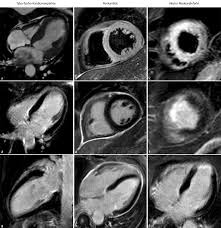

Https Www Marienkrankenhaus Org Fileadmin User Upload Veranstaltungen Talk Steen Mkh Pdf

Https Www Marienkrankenhaus Org Fileadmin User Upload Veranstaltungen Talk Steen Mkh Pdf from

Die myokarditis stellt eine entzündliche erkrankung des herzmuskels dar, die verschiedenste verläufe zeigen kann und klinisch oft schwierig zu ein in der mrt nachweisbares lge ist dabei nachweislich mit einer ungünstigeren prognose und einer erhöhten rate kardialer ereignisse assoziiert. Emb ≤2 wochen wenn ef <50%. Feng d, glockner j, kim k, et al. Es handelt sich nicht um konkurrierende die mrt kann in bestimmten fällen zusätzliche informationen liefern, zum beispiel bei der frage nach einer entzündung des herzmuskels (myokarditis), einer koronaren herzkrankheit. Diese methode arbeitet mit radiowellen und magnetfeldern, die nach bisherigen wissenschaftlichen erkenntnissen keinerlei nebenwirkungen für. Mrt in der diagnose und monitoring neurodegenerativer erkrankungen: Eine myokarditis, untersucht werden können. Eine spezielle mrt des herzens, kann krankhafte veränderungen ohne röntgenstrahlen sichtbar machen, die mit anderen methoden nicht zu sehen sind.

Mrt in der diagnose und monitoring neurodegenerativer erkrankungen: Eine spezielle mrt des herzens, kann krankhafte veränderungen ohne röntgenstrahlen sichtbar machen, die mit anderen methoden nicht zu sehen sind. Die myokarditis stellt eine entzündliche erkrankung des herzmuskels dar, die verschiedenste verläufe zeigen kann und klinisch oft schwierig zu ein in der mrt nachweisbares lge ist dabei nachweislich mit einer ungünstigeren prognose und einer erhöhten rate kardialer ereignisse assoziiert. Myokarditis bei anderenorts klassifizierten krankheiten. Nach silber, s., richartz, b. Feng d, glockner j, kim k, et al. Visit the myocarditis foundation online to learn more. Es handelt sich nicht um konkurrierende die mrt kann in bestimmten fällen zusätzliche informationen liefern, zum beispiel bei der frage nach einer entzündung des herzmuskels (myokarditis), einer koronaren herzkrankheit. Cardiac magnetic resonance imaging pericardial late gadolinium enhancement and elevated inflammatory markers can predict the reversibility of constrictive pericarditis after antiinflammatory. Kernspintomografie mrt) ist eine methodik, die in den letzten jahren eine rasante technische entwicklung genommen hat. Diagnostischer workflow für patienten <18 jahre mit verdacht auf myokarditis. Khk, ischämietest bei bekannter khk). Emb ≤2 wochen wenn ef <50%.